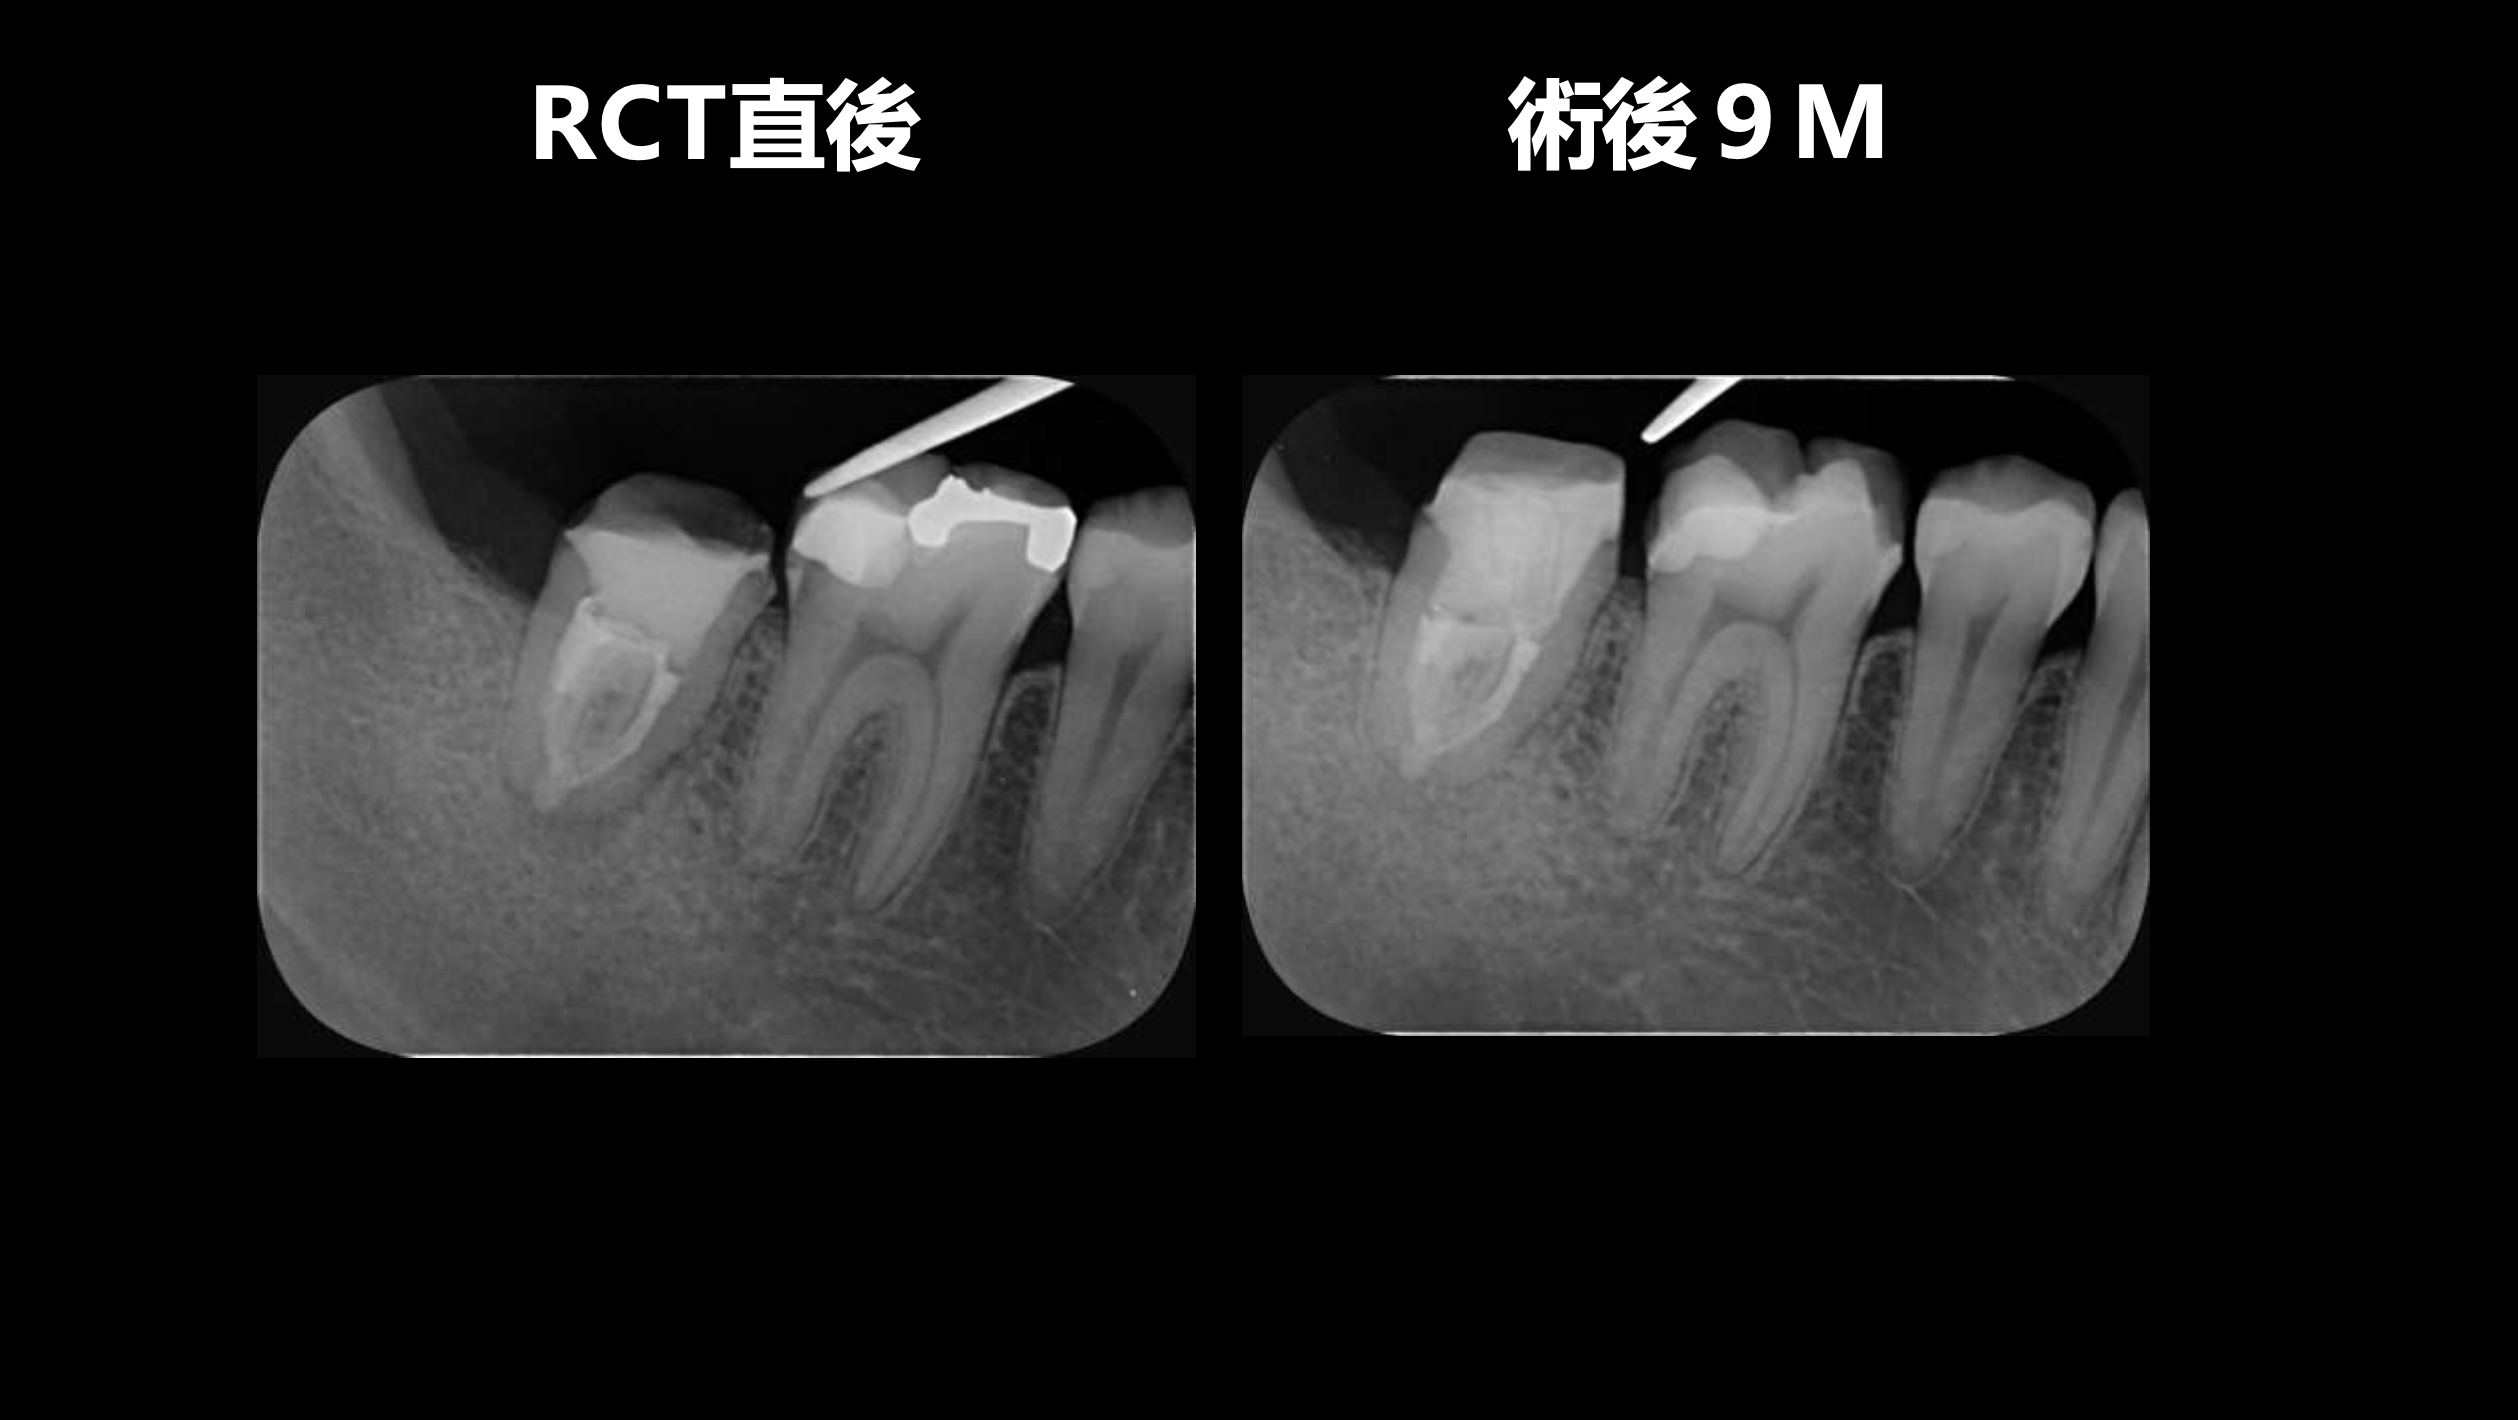

#10のRCTと3M recallである。

#9,10と病変があるが、

#9はColdに2秒で反応し、その痛みが5秒でおさまったことから生活歯と判断し、

Cold, EPTに反応がなく打診痛もある#10を患歯と考え、#10のみ根管治療することとなった。

その際の成功率は86%である。

と術前に患者さんに告げて治療へ導入し以下のようになった。

3ヶ月しか経過していないが根尖病変は大きく減少した。

治療していない#9には変化があまりないがだからと言って手をつける必要性はない。

患者に症状がないからだ。